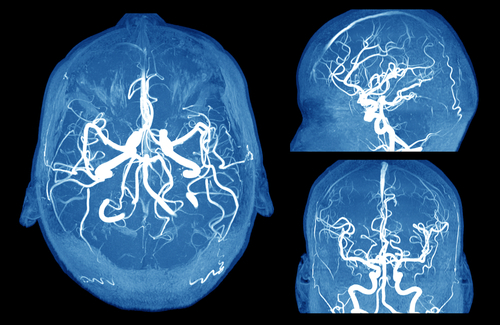

Apollo Hospitals, Chennai on June 5 said it had successfully treated dysplastic giant brain aneurysm on a 54-year-old software engineer with Neuro-Endovascular surgery.

The patient, a resident of Vembangudi in Thanjavur, currently working in Dubai developed mild headache and drooping left eyelid. He was diagnosed with a large aneurysm in the brain and Dr Srinivasan Paramasivam, Senior Consultant Neurosurgeon, performed the Neuro-Endovascular Surgery to treat the aneurysm that would have ruptured causing severe brain injury and even death.

Talking to reporters here, Dr Srinivasan Paramasivam said the patient had developed, headache, drooping of left eyelid along with double vision that required immediate medical attention. After doctors in Dubai diagnosed him with a large aneurysm in the brain, he flew into the Apollo hospitals as the condition required immediate neuro-surgical care.

A brain aneurysm is a bulge or ballooning of a blood vessel in the brain and it could leak or rupture, causing bleeding into the brain (hemorrhagic stroke), he said. He said most often a ruptured brain aneurysm occurs in the space between the brain and the thin tissues covering the brain. This type of hemorrhagic stroke is called a subarachnoid hemorrhage. A ruptured aneurysm quickly becomes life-threatening and requires prompt medical treatment.